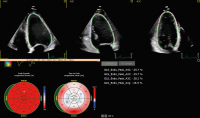

Die standardisierte Echokardiographie: Durchführung, Archivierung und Befunderstellung sowie Evaluierung der systolischen Linksventrikelfunktion // Standardised Echocardiography

Journal für Kardiologie - Austrian Journal of Cardiology 2024; 31 (5-6): 96-103 Volltext (PDF) Summary Abbildungen